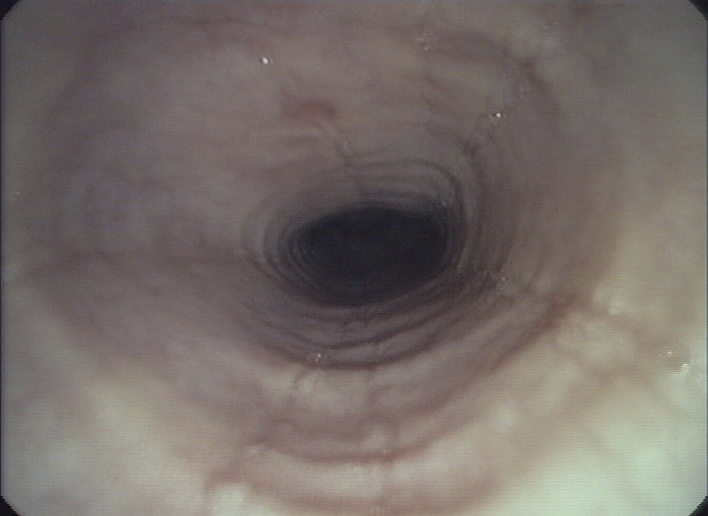

Figure 1

Endoscopic pictures illustrating the major endoscopic signs of EoE:

Panel A illustrates the endoscopic appearance of a healthy esophagus. Panel B represents a moderate inflamed esophagus with edema, longitudinal furrowing and mild non-stenosing trachealisation. Panel C shows a severe inflamed esophagus with edema, white exudates and deep furrowing. Panel D illustrate signs associated with remodeling such as stricture due to fixed esophageal rings.